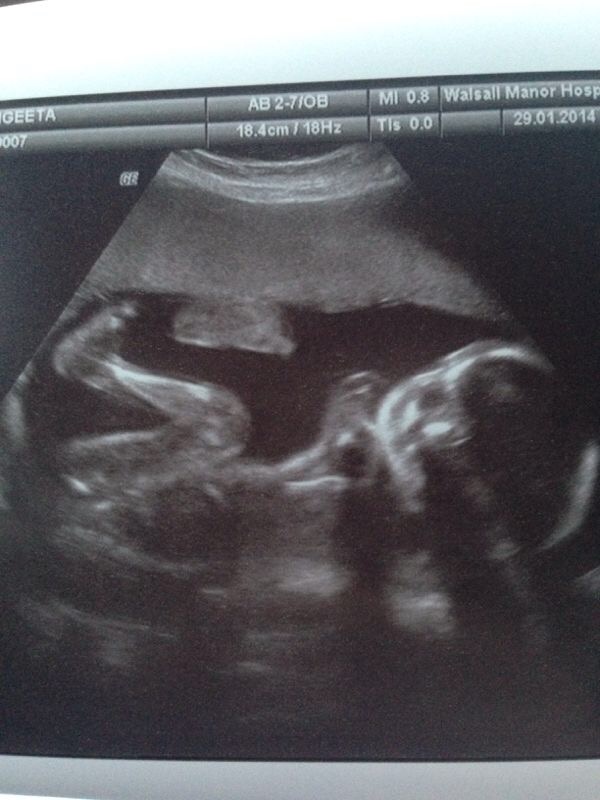

We tracked the development of Sid using an app called babybump, and it was great. Week by week I took photos of Sang and tracked her development up till his arrival.

This is about as much as most guys I’ve spoken to get involved. For me,this wasn’t enough. I often think that mums to be get the opportunity to develop a unique bond with their child, way before it pops out. They get to feel the baby and talk to the baby, they share a heart beat, and other bodily fluids.

But dads, it feels like we kind of sit there twiddling our thumbs before we can connect to the baby, which happens after its out in this world, and at this time you’re fighting off all other relatives to get time with him…

Me, well my family say that I’ve been broody since the age of 19 (probably true) and so this journey was one waited for patiently and I wanted to get connected to Sid as soon as possible.

I thought I’d list a few things that I would do, every evening, to connect with Sang and the growing baby, to develop a bond as a prenatal family.

These things kept me close to her, and I feel gave me a great connection to Sid before he arrived in June ’14.

1. Listen to the bump. Every evening I would stick my ear to Sangs abdomen to try and hear the baby swishing around. More often than not, especially for the first few months, I just got Sangs sloshing tummy thanks to her hyperemesis (a whole other blog). But as the foetus developed, i would get the occasional punch or kick from Sid- probably won’t to my weighty head resting on him too much.

2. Talk to the bump, really close up. Sid was a great listener. I did at times feel a little stupid talking to him, but being able to tell him about the outside world, how beautiful his mummy is, and let him hear another voice was a great feeling. For me it was a connection to him that I developed over time and I think it explains why he doesn’t bother listening to me now!